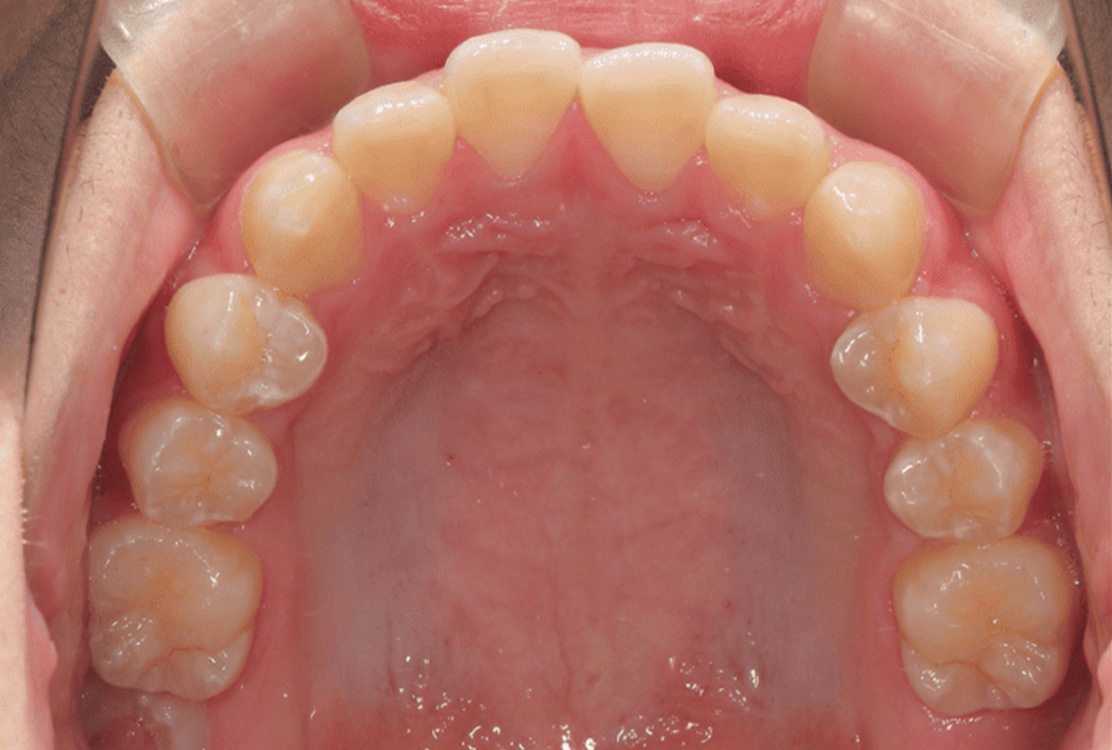

治療後